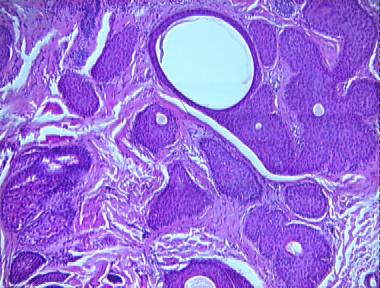

trichoadenoma

Histologic Features